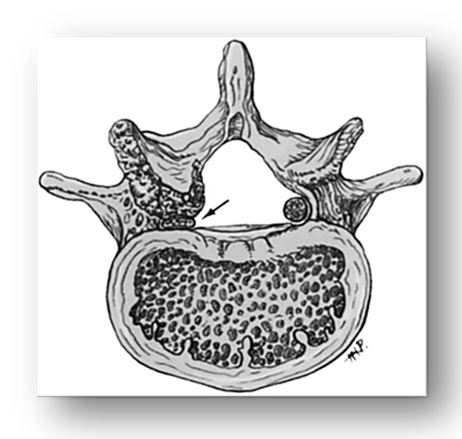

Lateral stenosis: Lateral spinal stenosis is a common cause of lumbar radicular pain syndromes. The lateral lumbar spinal column includes the nerve root canal (lateral recess) and the intervertebral foramen (neural foramen). These two areas together form a tubular canal through which the nerve root exits [7, p. 313-320] (fig. 2).